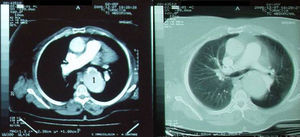

Over the course of three years, several computed tomography (CT) scans were performed, which showed no progression of the aneurysm (Figure 1).

However, in 2005, the hypertension became uncontrolled and the patient developed symptoms of heart failure (exertional dyspnea, fatigue, orthopnea) and was referred to the outpatient hypertension clinic. On physical examination she was obese (BMI 35kg/m2), with high blood pressure (170/100mmHg) in the upper limbs and unmeasurable in the lower limbs due to extreme obesity, and tachycardic, with irregular arrhythmic pulse; cardiopulmonary auscultation revealed arrhythmic heartbeats (with no murmurs) and inspiratory bibasal crackles; and lower limb edema was evident. On initial complementary workup the ECG revealed atrial fibrillation and voltage criteria of LVH, and the echocardiogram disclosed LVH, non-dilated LV with preserved systolic function, mild aortic regurgitation (tricuspid aortic valve) and normal right-side chambers and valves; laboratory tests were normal, including renal function; the renal ultrasound was also normal. Despite treatment with several antihypertensive drug combinations, including ACE inhibitors, ARBs, chlorthalidone, furosemide, spironolactone, beta-blockers and calcium antagonists, her blood pressure remained uncontrolled. At that time another CT was performed which showed no progression of the aortic aneurysm.